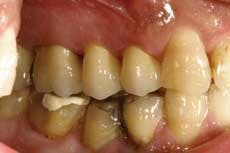

Wol-Ceram is now available from many national laboratories, and even if your local laboratory does not have Wol-Ceram, they can have the copings fabricated by one of the large laboratories. Wol-Ceram is the first all-ceramic system that allows you to prepare teeth with a featheredge margin; shoulders and chamfers are not required. Many dentists have complained about the extra preparation required for most all-ceramic restorations, feeling that a standard PFM preparation should be adequate reduction.

From the very first three units I cemented, I knew there was something special about the Wol-Ceram system. These were the first all-ceramic crowns I had ever inserted that felt like PFMs as they slid down into place. There is nothing quite so reassuring as being able to feel the mechanical retention of a crown as it moves down the prep.